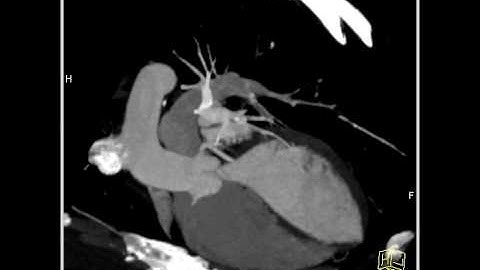

Instant Volume Visualization using Maximum Intensity Difference Accumulation (1)